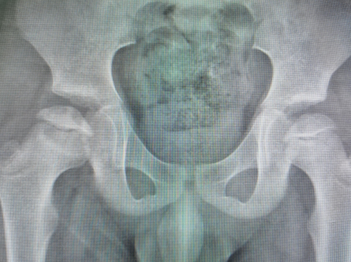

术中X线

术后X线